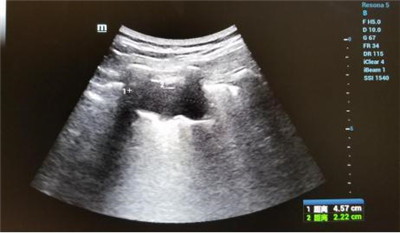

患者郑女士,在乐鱼在线登录入口被确诊肺癌,癌肿位于左肺下叶近胸膜处,大小约4.5x2.2cm,经化疗后肿块变化不明显。肿瘤外科二病区王雅辉副主任医师与超声科刘晓晖主任医师会诊后,认为可以为患者施行超声引导下肺癌微波消融术,因为属于首例,特邀西京医院王建宏教授进行术中指导,超声科华玺主治医师进行引导,麻醉手术科李万鹏副主任进行术中监测,降低手术风险,提高肿瘤综合治疗效果。整个治疗过程约30分钟,患者术中术后生命体征平稳。